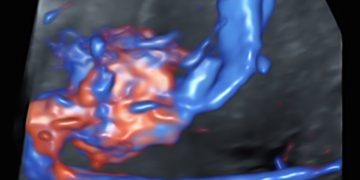

How To Do Luglio 2023: terminologia e classificazione MUSA

Cari soci, questo mese un nuovo video "How to do", dedicato alla terminologia e classificazione MUSA Grazie a Francesca Arezzo! Il video è accessibile ai soli soci SIEOG attraverso questo...